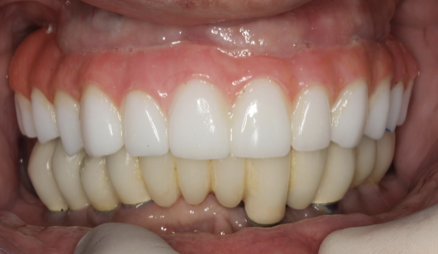

(13.) Prosthetic design allowing access to FMG interface.

Figure 13

(14.) Healthy Gingival Tissue.

Figure 14

(15.) FMG access and convex intaglio profile.

Figure 15

(16.) FMG access and convex intaglio profile.

Figure 16